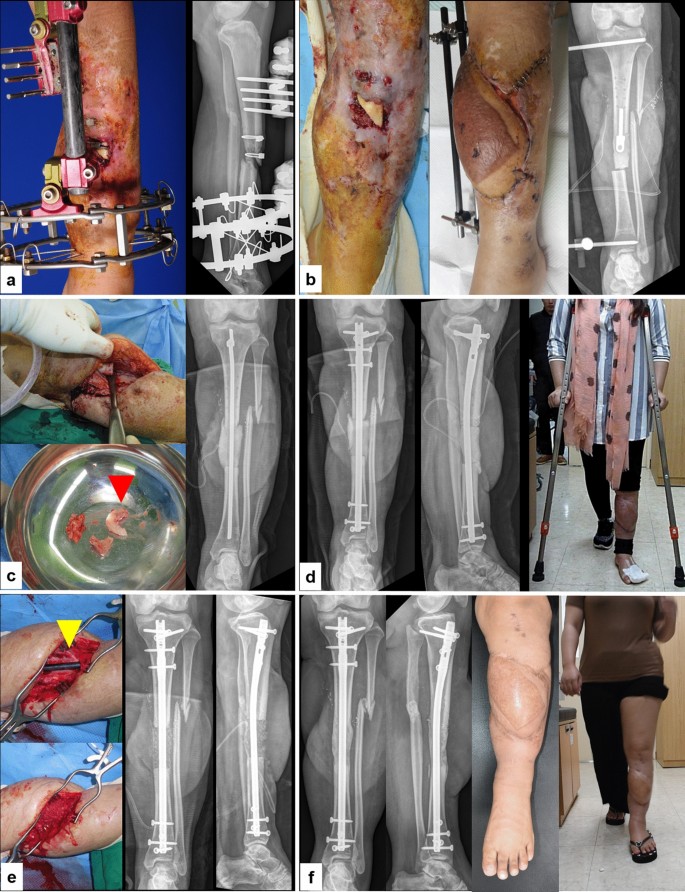

(a) A 24-year-old female patient sustained a recalcitrant infected nonunion of the left tibia. (b) According to the Multi-staged IMT protocol, we performed thorough debridement, placed an antibiotic-loaded PMMA spacer, and provided temporary bony stabilization. Soft tissue defects were covered using an anterolateral thigh flap (stage 1). (c) As PDCP had been identified at EMP and IMP (pseudomonas and MRSA), targeted debridement at proximal area of bone defect (red arrow head, sequestrum) and temporary fixation using antibiotics loaded PMMA coated intramedullary rod was performed (repetitive stage1). (d) After confirming all PDCN at previous stage, definitive fixation using IM nail was performed. An antibiotic-loaded PMMA spacer was reinserted into the bone defect for staged bone grafting to confirm that the infection had been eradicated (stage 2). Prompt partial weight bearing exercise was allowed after definitive fixation. (e) The 6-cm sized segmental bone defect was filled with autogenous bone (45 g) and DBM (15 g) in induced membrane chamber (yellow arrow head) at 16 weeks after stage 2 (stage 3). (f) Two years follow up radiographs show complete consolidation of the grafted bone without recurrent infection. The injured limb recovered to full function.